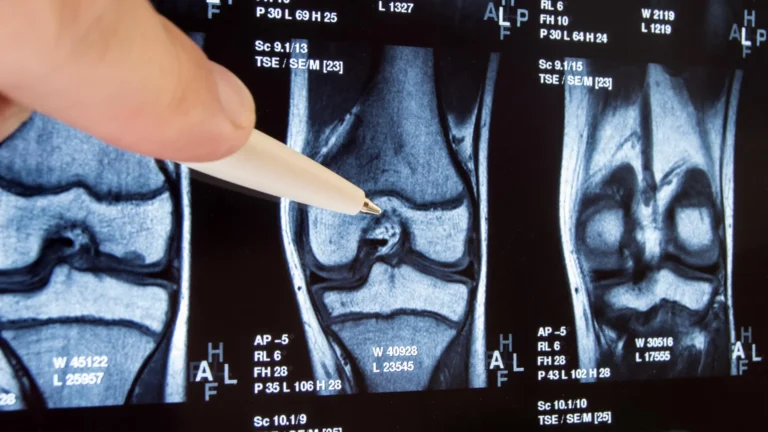

Jeffrey Sturek, MD, PhD, a physician-scientist at UVA who contributed significantly to this collaborative study, underscored the clinical relevance of these findings: "These results carry immediate and substantial implications for how we approach patient monitoring in the aftermath of severe viral respiratory infections. For decades, we have recognized established risk factors for lung cancer, such as tobacco use. This research suggests that severe viral respiratory infections may warrant similar consideration in risk stratification. For instance, in individuals with a substantial smoking history, we routinely recommend proactive surveillance, including regular low-dose CT scans of the lungs, to ensure early detection. Future research may well explore the feasibility and necessity of analogous surveillance protocols following severe viral respiratory illness."